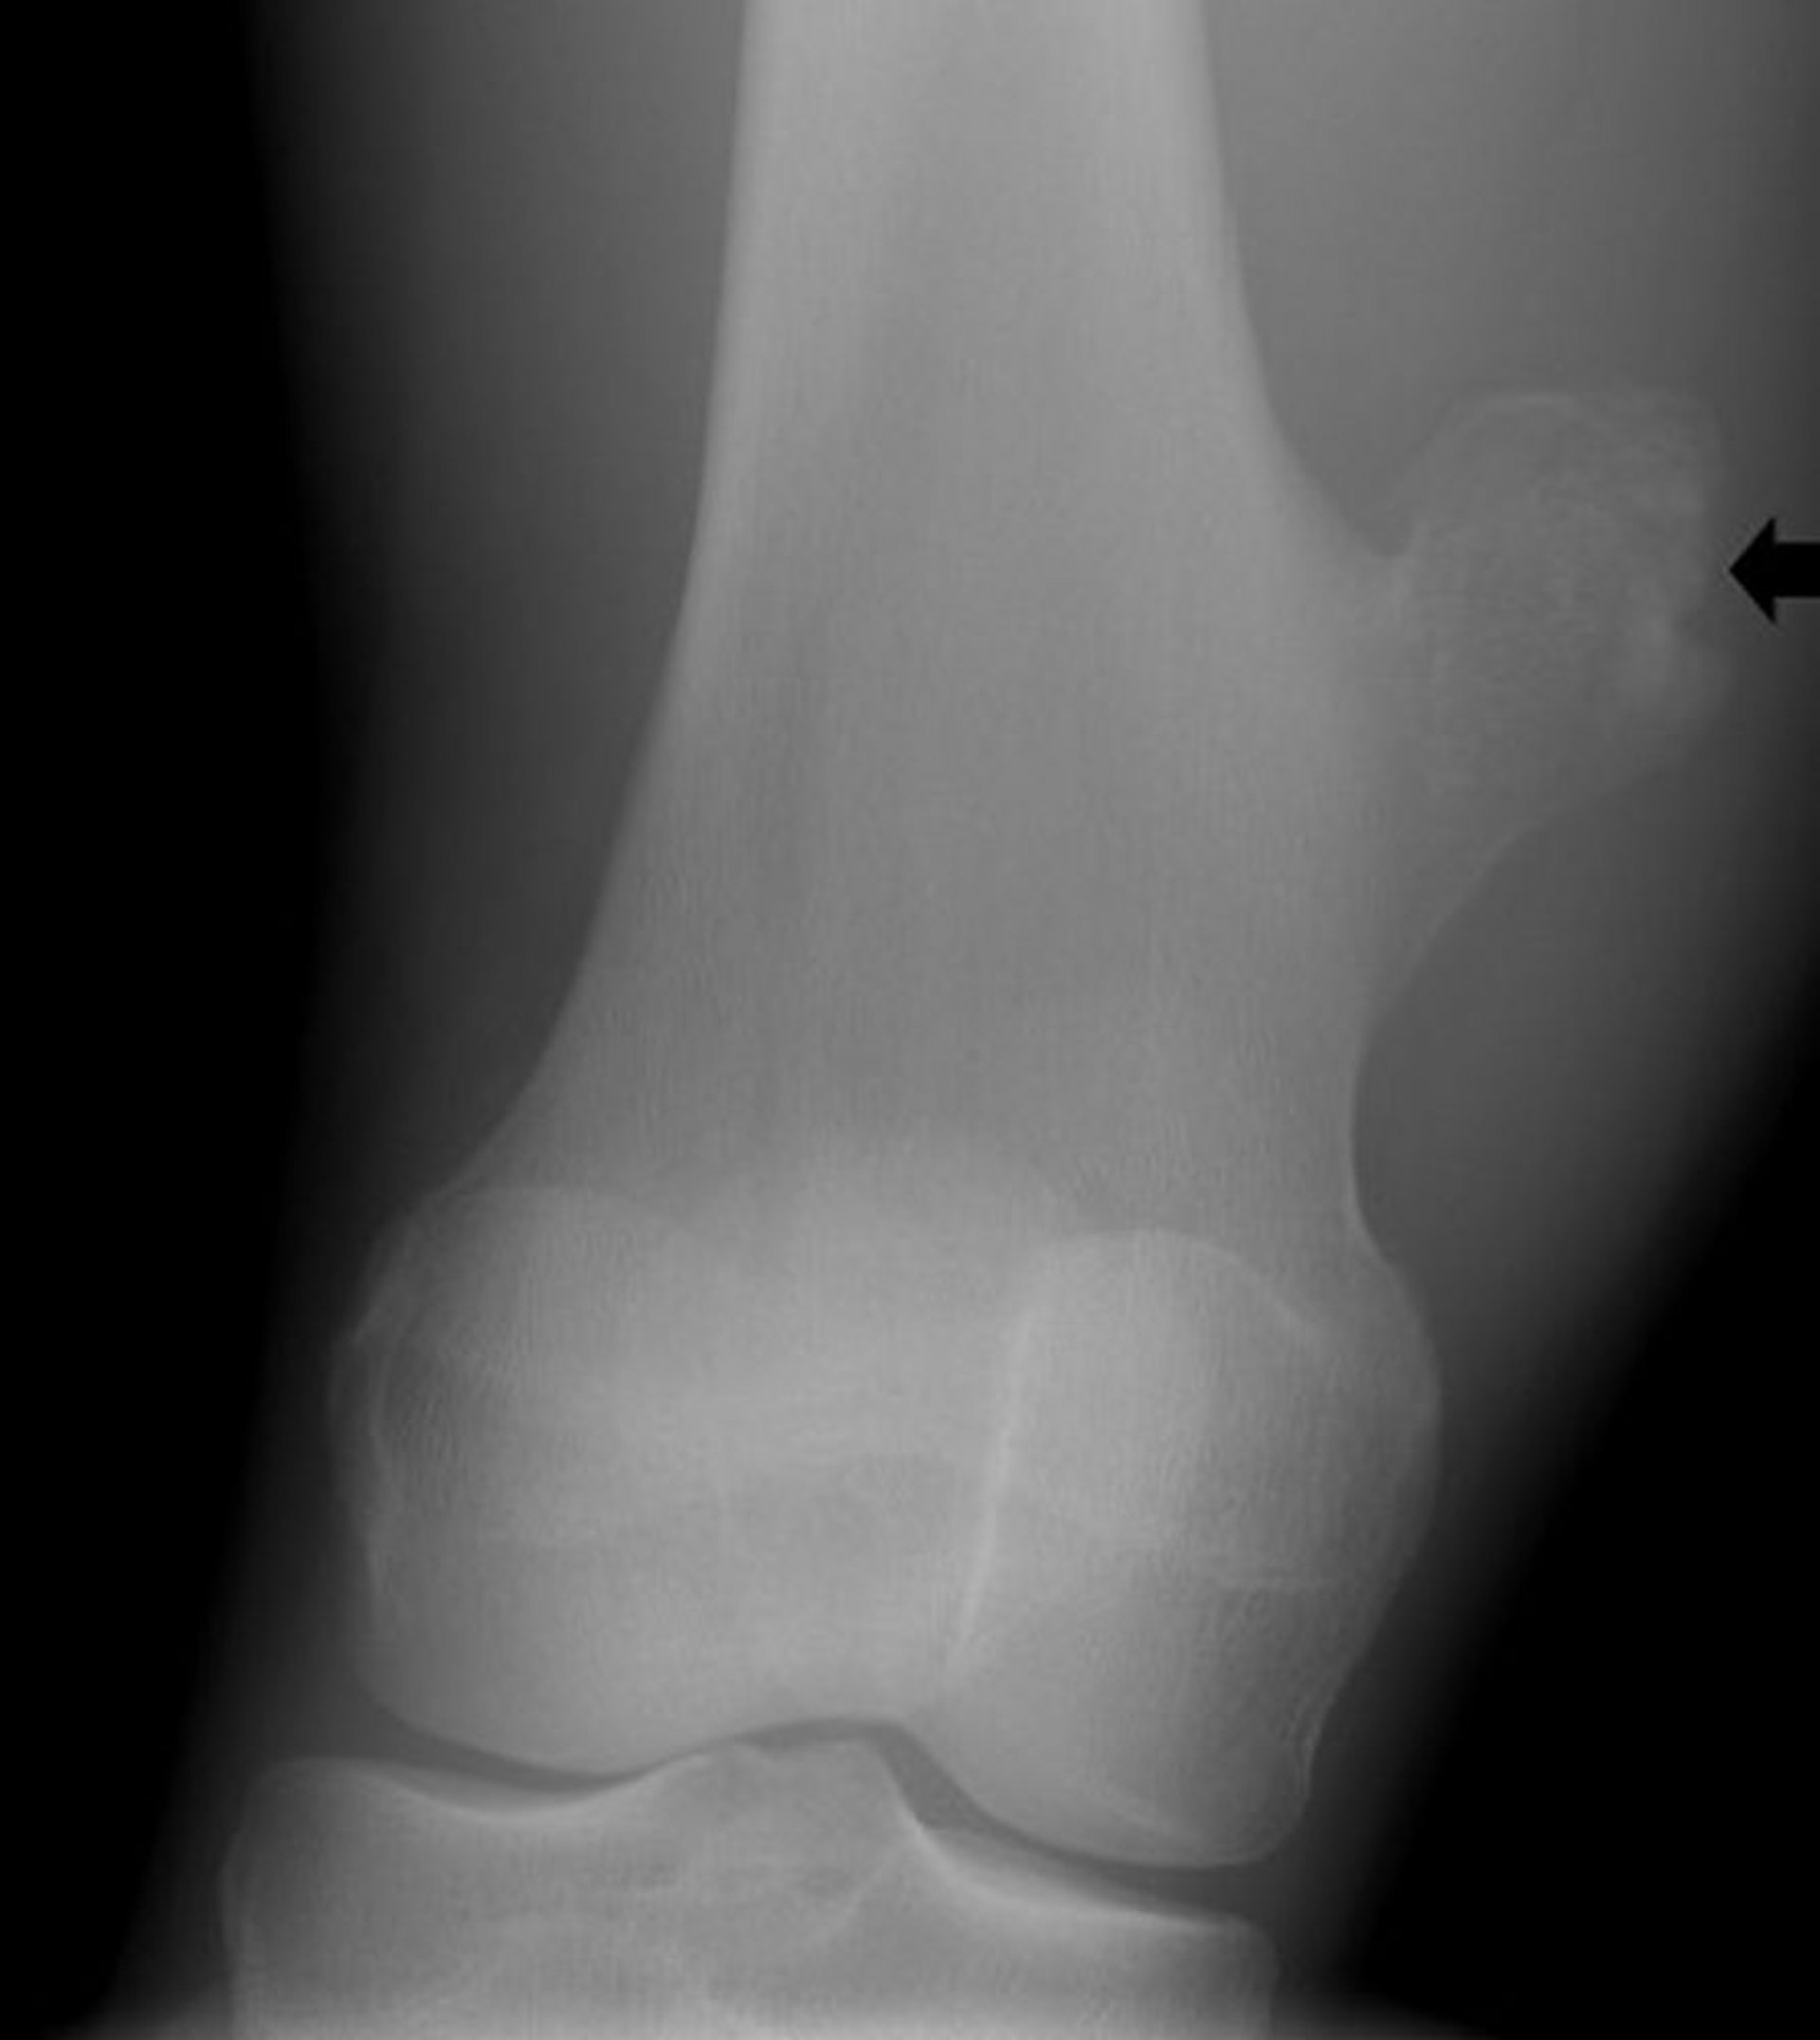

Ostéochondrome du genou

Cette radiographie du genou montre une excroissance osseuse (flèche) du fémur au-dessus de l'articulation du genou qui est compatible avec un ostéochondrome.

Image courtoisie de Michael J. Joyce, MD, and Hakan Ilaslan, MD.